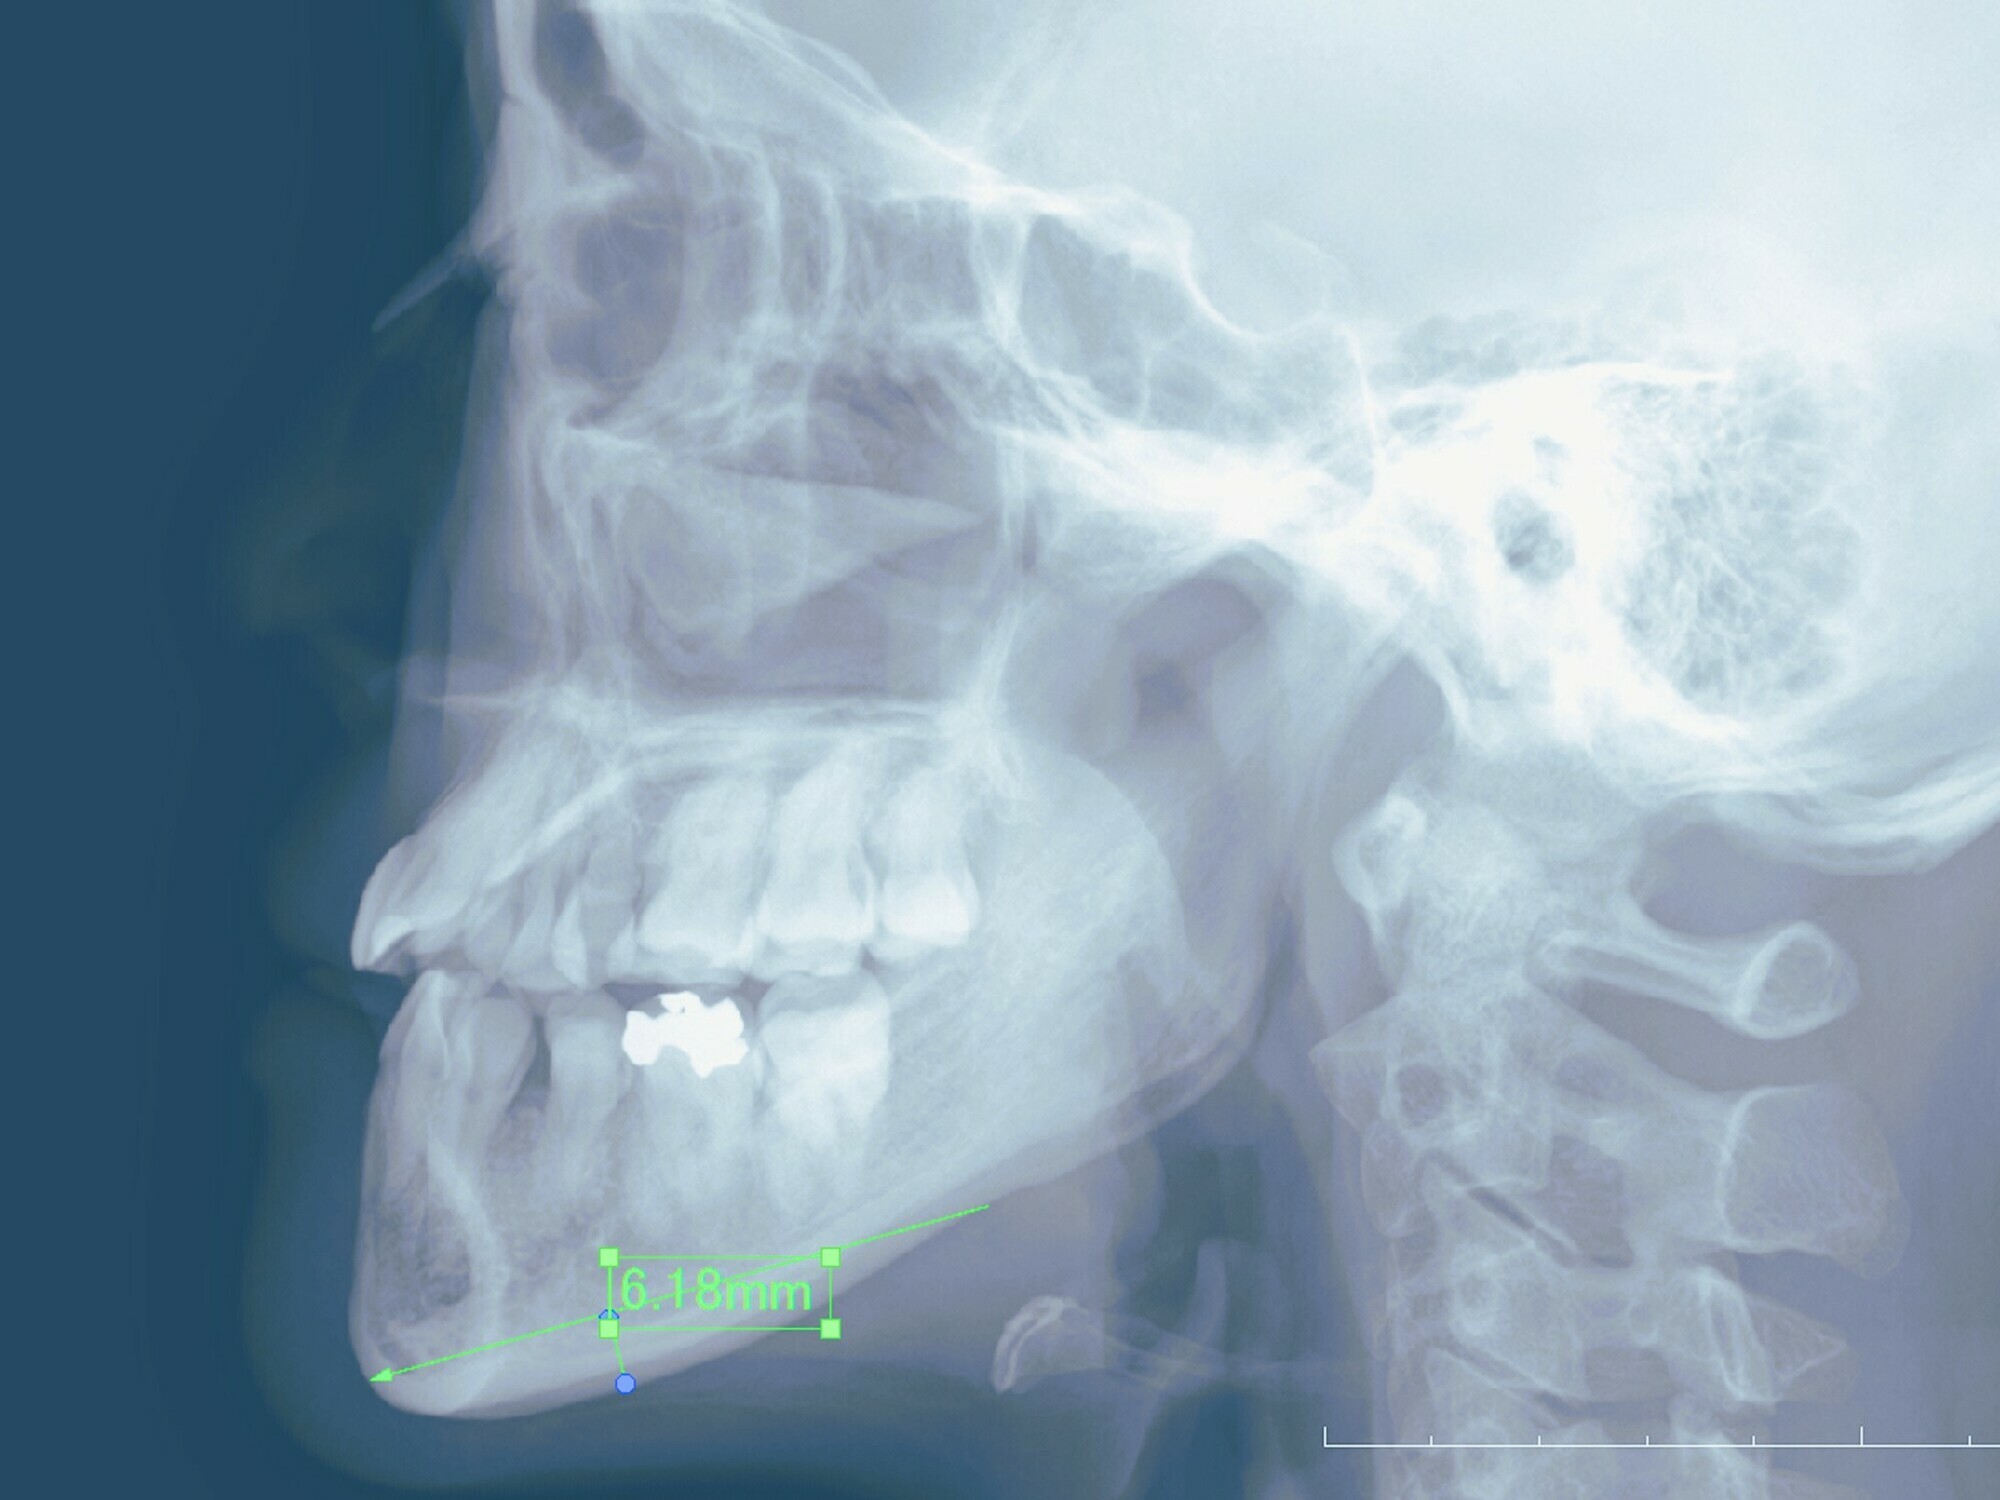

30代女性の下顎骨ブーメラン型骨切り+頬脂肪吸引症例になります。顎を短くしたい、小顔にしたいとの希望にて、前記手術を行っています。 頬脂肪吸引は下顎骨骨切りと同時に行うことによって、頬のたるみを少なくすることが可能です。 骨切りは、右最大幅6.5mm 左最大幅6mmにて、ブーメラン型に切っています。 レントゲンによるシュミレーションとほぼ同じ形で切り出すことが可能です。